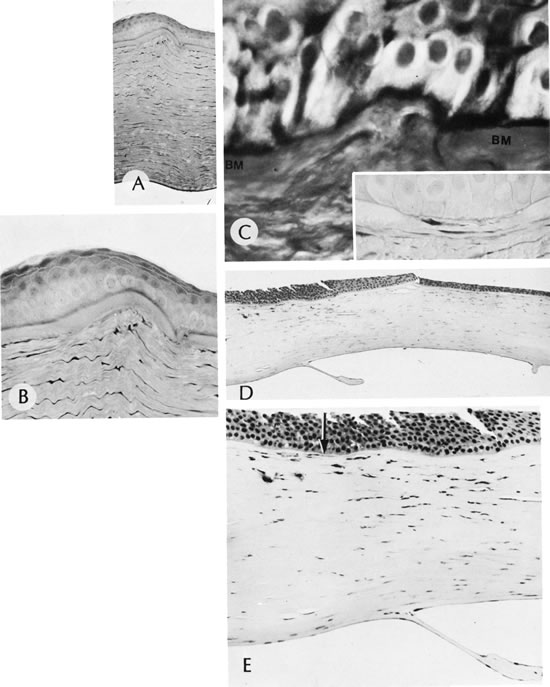

Reis-Bucklers' dystrophy, also called anterior limiting membrane dystrophy, is a primary abnormality of Bowman's membrane, resulting in replacement of the native membrane with layers of abnormal collagenous tissue.135 This autosomal dominant disease is expressed clinically in early childhood by painful recurrent erosions. The episodes continue to occur through the first and second decades of life and then become quiescent, only to recur in the fifth and sixth decades. Following multiple episodes, the abnormal Bowman's membrane is seen as a subepithelial translucent layer with diffuse corneal scarring (CDB-I) and a honeycomb pattern (Thiel Behnke corneal dystrophy—CDB-II) due to the deposition of abnormal collagen.136

Loss of hemidesmosomes of the basal squamous epithelium can be seen with electron microscopy in early cases. An abnormal material composed of peculiar “curly filaments” is produced at the basal lamina of the epithelial cells in CDB-II.137 In more advanced cases, Bowman's membrane appears by light microscopy to be focally digested, a pattern similar to that seen in corneal stromal dystrophies, which are associated with recurrent erosion. Bowman's membrane ultimately may be replaced completely by reparative collagenous tissue. The corneal stroma in CDB-I and CDB-II are normal (Figs. 27 and 28). Electron microscopy of CDB I reveals granular type opacities.CDB I has been localized to chromosome 5q31 and CDB II to chromosome 10q23-q24.138,139 Streeten has shown that both the granular or rod-shaped deposits in Reis-Bucklers' dystrophy and the “curly fibers” of Thiel-Behnke dystrophy are immunoreactive for BIGH3 protein, consistent with mutations in the BIGH3 gene.140

Fig. 27. Reis-Bucklers'dystrophy (corneal dystrophy of Bowman type II [CDB-II]). A. Early stage shows small, white dots in continuity with the band of relucency representing Bowman's membrane. Biopsy (inset) is oriented to correspond to drawing. Bowman's membrane (b) is destroyed at the top. B. Moderately advanced stage shows confluence of the whitish subepithelial mounds in the characteristic honeycombed pattern. C. The abundant subepithelial tissue composed of peculiar curly filaments is highly characteristic of the entity. The filaments are closely interwoven, with regions of thin basement membrane. Hemidesmosomes along the epithelial basal cell (EP) are fewer than normal. The basilar cell processes are abnormal. Inset shows degeneration of Bowman's membrane in several foci (arrows indicate membrane remnants). The thick, avascular, fibrous membrane present under the epithelium forms mounds that produce a typical honeycombed pattern in three dimensions. (Courtesy of SEI Photoarchives.) (A modified from Griffith DG, Fine BS: Light and electron microscopic observations in a superficial corneal dystrophy: Probable early Reis-Buckler's type. Am J Ophthalmol 63:1659, 1967; B and C modified from Perry HD, Fine BS, Caldwell DR: Reis-Buckler's dystrophy: A study of eight cases. Arch Ophthalmol 97:664, 1979.)

Fig. 28. Reis-Bucklers' dystrophy. A. Late-stage Reis-Bucklers' dystrophy. B. Bowman's membrane (arrow) has degenerated, and a heavy subepithelial pannus has formed. The remainder of the stroma is normal. Inset shows high magnification of the area where Bowman's membrane has been destroyed. (Courtesy of SEI Photoarchives.)